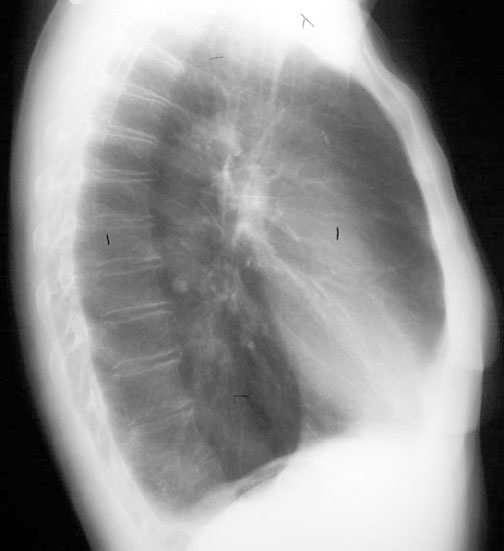

| CXR | Identify left and right. | What are the findings that help in making that decision. | Answer |

| CXR | Which diaphragm is higher in the lateral view in a normal? | How do you explain it? | Answer |

| CXR | Are both diaphragms visible in lateral view? | What is the significance if one diaphragm is not visible? | Answer |